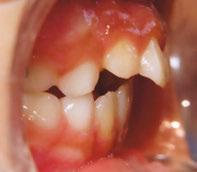

The following procedures were accomplished under general anesthesia on an outpatient basis — full mouth dental radiographs and a comprehensive oral exam. A complex odontoma was found to be the etiology of the noneruption of the maxillary right permanent central incisor (Figure 2). Since dental caries also was diagnosed, a full-mouth prophylaxis was completed. Dental caries was controlled, and teeth were restored. A 5 mm incision was made on the gingiva over the impacted maxillary right permanent central incisor, and two tooth-like structures were extracted from the right maxillary incisor area. A postoperative periapical radiograph was taken to confirm complete odontoma removal (Figure 3). Three interrupted sutures using 3-O chromic gut were placed.

At the postoperative consultation with the mother, we told her the tooth’s complete root formation might prevent its eruption. Orthodontic extrusion of the incisor was ruled out due to his behavior. A conservative approach with observation only was elected as treatment modality. This patient returned for follow-up appointments at ages 10, 11, 12, and 13. During all these visits, the maxillary right permanent central incisor had not erupted. At age 14, due to recurrent dental caries, the patient was taken to the local children’s hospital for dental rehabilitation again. During this second hospitalization, we noticed that the right maxillary central incisor was partially erupted into the oral cavity (Figure 4).